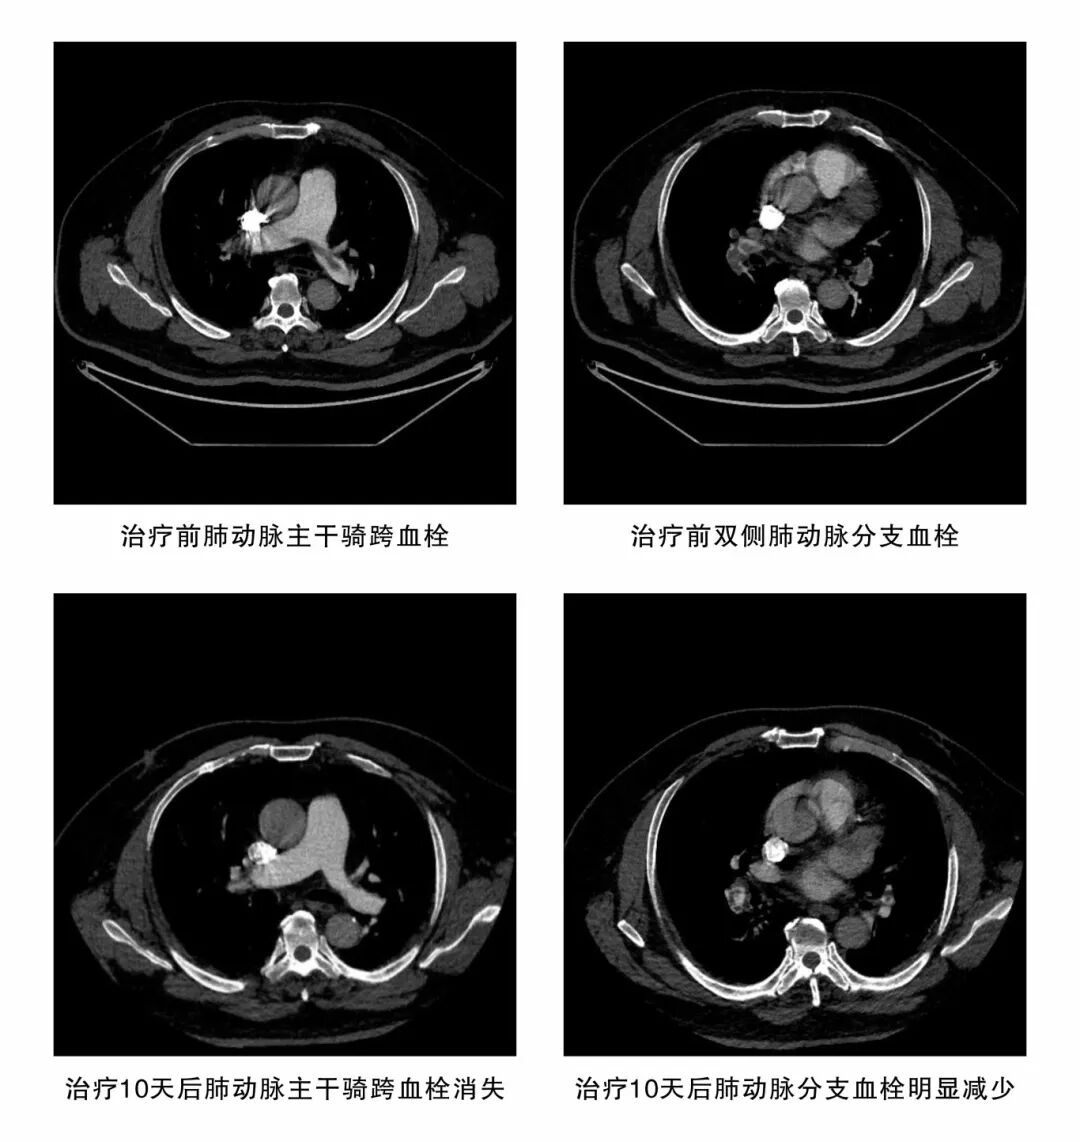

11月1日,一名50多歲的男性患者因“突發(fā)心慌、氣喘2天”被緊急轉(zhuǎn)入潛江市中心醫(yī)院。急診團(tuán)隊(duì)迅速識(shí)別病情并立即開(kāi)啟綠色通道。檢查結(jié)果令人震驚:血液D-二聚體飆升至6.61mg/L(遠(yuǎn)超正常標(biāo)準(zhǔn)),強(qiáng)烈提示血栓形成;肺動(dòng)脈 CTA 影像更令人揪心——雙肺肺動(dòng)脈從主干到分支布滿多發(fā)栓塞,最大栓子體積達(dá) 22.78cm3,右心室已明顯擴(kuò)大?;颊卟∏楫惓措U(xiǎn),如同肺部布滿“炸彈”,隨時(shí)可能引爆,造成呼吸循環(huán)衰竭,導(dǎo)致猝死。

功夫不負(fù)有心人。在醫(yī)護(hù)團(tuán)隊(duì)的精心治療與細(xì)心守護(hù)下,患者的病情一天天好轉(zhuǎn)。11月11日復(fù)查肺動(dòng)脈CT影像傳來(lái)捷報(bào),患者肺部血栓已明顯吸收;11月19日,患者自覺(jué)胸悶、氣喘癥狀已顯著緩解。當(dāng)停用肝素的那一刻,整個(gè)醫(yī)護(hù)團(tuán)隊(duì)?wèi)抑男慕K于落下。